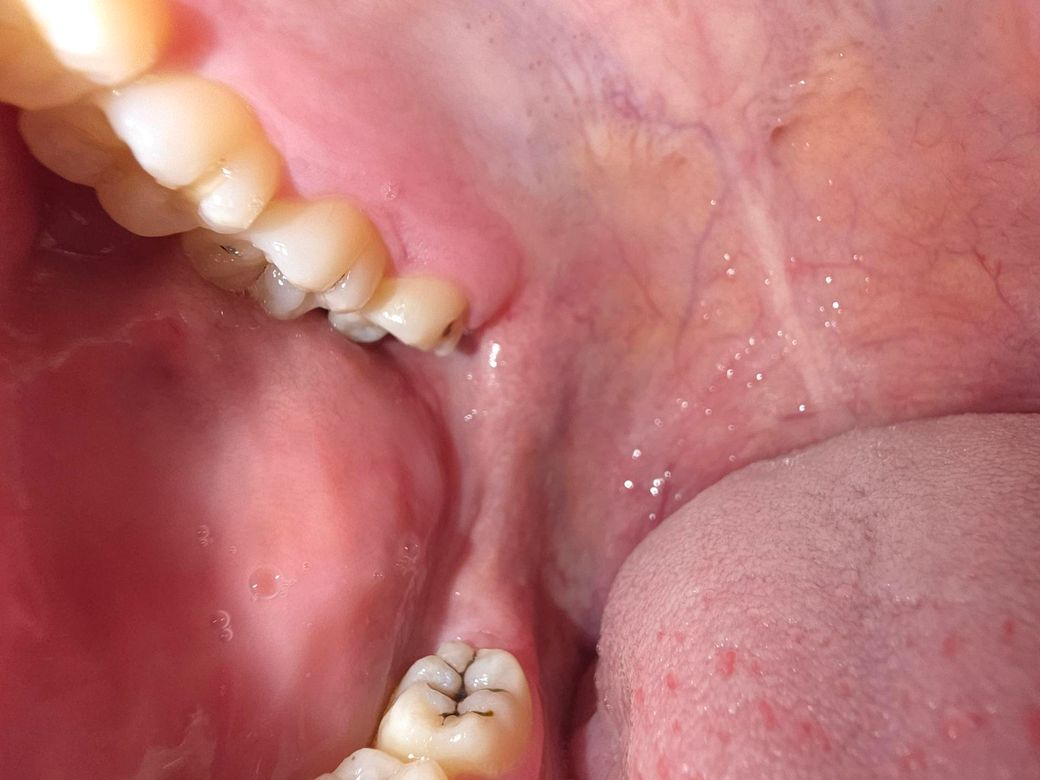

충치 발치해야할정도인가요? 충치가 너무 많이 진행됐어요

제가 양치하는 습관을 안들여놔서 이빨에 치석도 있고 충치도많은데요 충치가 있는 상태에서 치과를 안간지 몇년이 됐더니 맨끝 어금니를 혀로 훑었을때 되게 파여있고 그 이빨에 음식물이 엄청 껴요 딱히 통증이 있거나 하진않은데 발치해야할 정도인가요?

• 1번 째 사진

사진으로 봤을 경우에는 충치가 깊은것으로 보이지는 않습니다.

하지만 정확한확인을 위해서는 치과에서 진료를 받아 보는것이 좋습니다.

발치해야할 정도는 아닐 것 같습니다 보통 충치 때문에 발치를 해야할 정도라면 치아가 거의 다 날라간 정도입니다